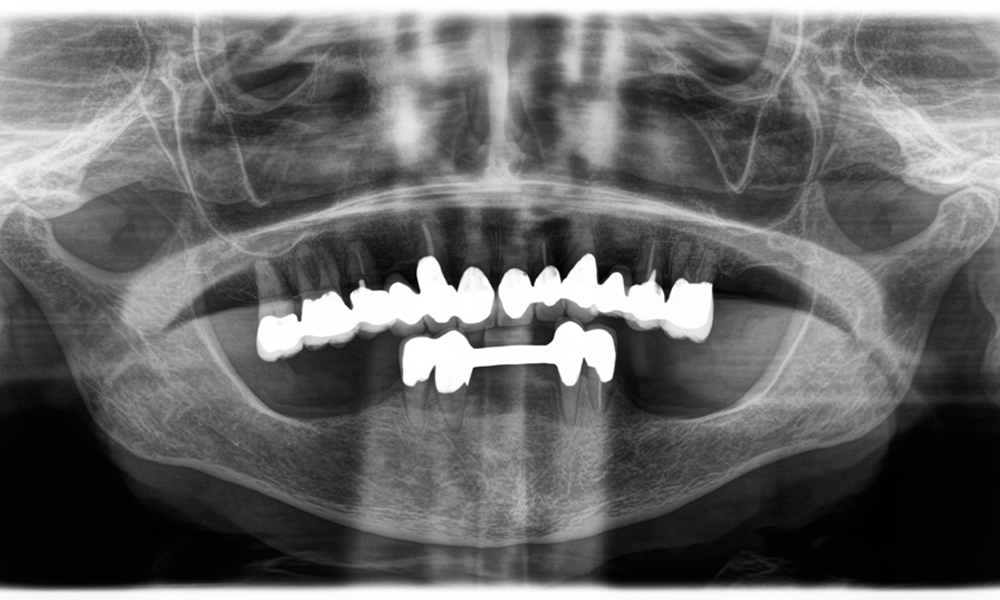

Dr. Wolfgang Tautschnig, ein erfahrener Zahnarzt aus Salzburg, hat die Synea Power Edition über mehrere Monate hinweg in seiner Praxis in verschiedenen klinischen Szenarien eingesetzt und evaluiert. Darunter vor allem für das Entfernen von Zirkonkronen und das Bearbeiten von unedlen Legierungen. In einem konkreten Fall stellte sich eine 81-jährige Patientin mit dem Wunsch nach einer ästhetischen Verbesserung ihrer 40 Jahre alten VMK-Kronen vor. Die bestehenden Kronen entsprachen nicht mehr den ästhetischen Ansprüchen der Patientin. Die Herausforderung lag in der Entfernung von zwölf verblockten Kronen mit unedler Legierung, ohne die darunterliegenden Zahnstümpfe zu beschädigen. Das Winkelstück wurde genutzt, um die Keramikschichten präzise einzuschlitzen sowie die Metallgerüste mit einem Hartmetallfräser zu trennen, um so die Kronen mit minimalem Trauma zu entfernen. Innerhalb von nur 30 Minuten waren die alten Kronen entfernt, danach konnte die neue Arbeit, bestehend aus Vollzirkon im Seitenzahnbereich und verblendeten Kronen im Frontzahnbereich, vorbereitet werden. Das Ergebnis war eine vollständige Neuanfertigung, die sowohl funktional als auch ästhetisch überzeugte (siehe Abb. 1).

Ein weiteres Beispiel für die klinische Leistungsfähigkeit der Power Edition war der Austausch einer beschädigten Zirkonkrone bei einer 63-jährigen Patientin. Diese stellte sich aufgrund eines abgesplitterten Verblendungsteils ihrer 20 Jahre alten Zirkonkrone an Zahn 6 vor. Trotz der Position im Seitenzahnbereich empfand die Patientin dies als störend und wünschte eine neue Krone.